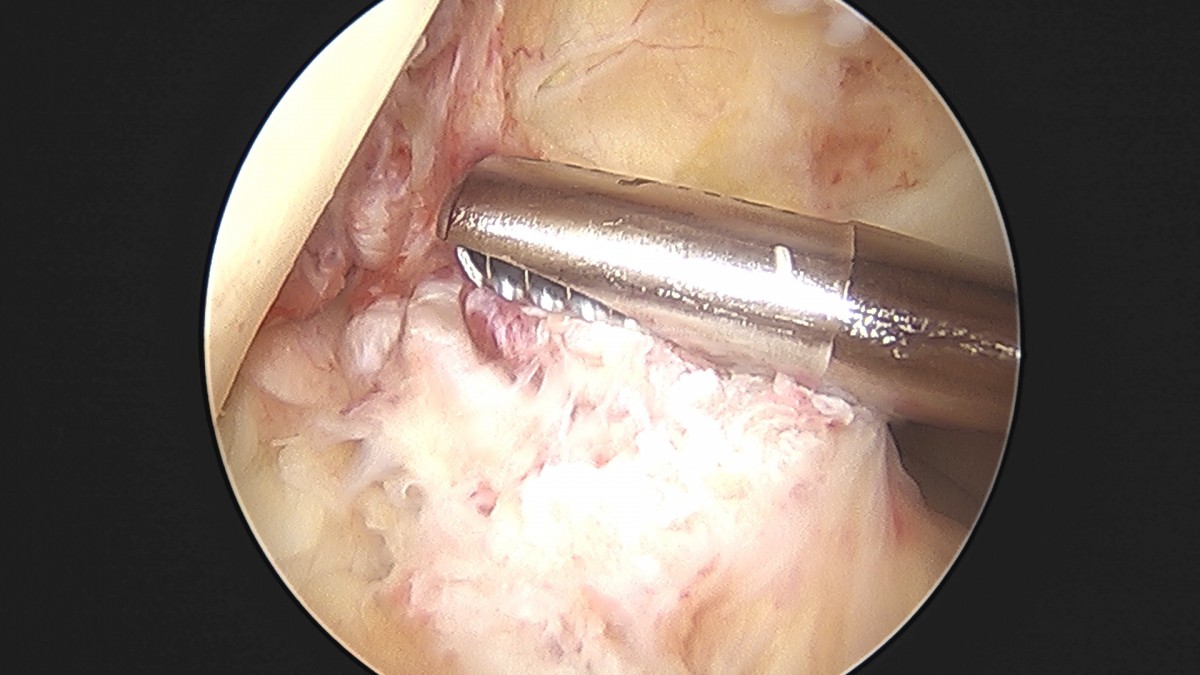

이재상원장님 전방십자인대 재건술 및 반월상 연골판 봉합술 윤두O 환자

작성자 최고관리자 댓글 0건 조회 704회 작성일 25-09-16 16:22